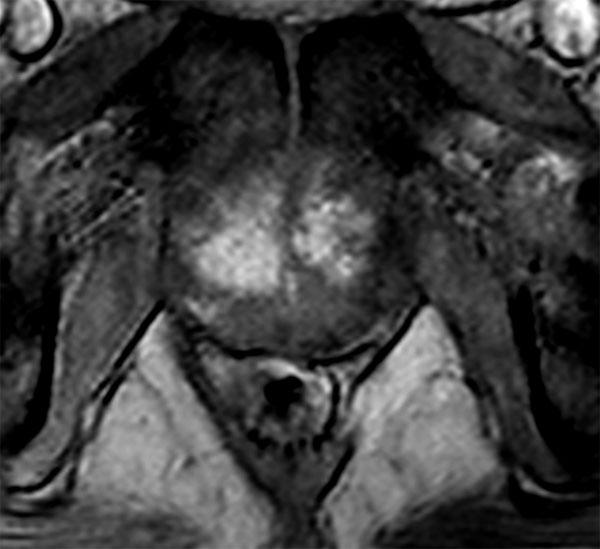

Axial dynamic T1w 3D TFE